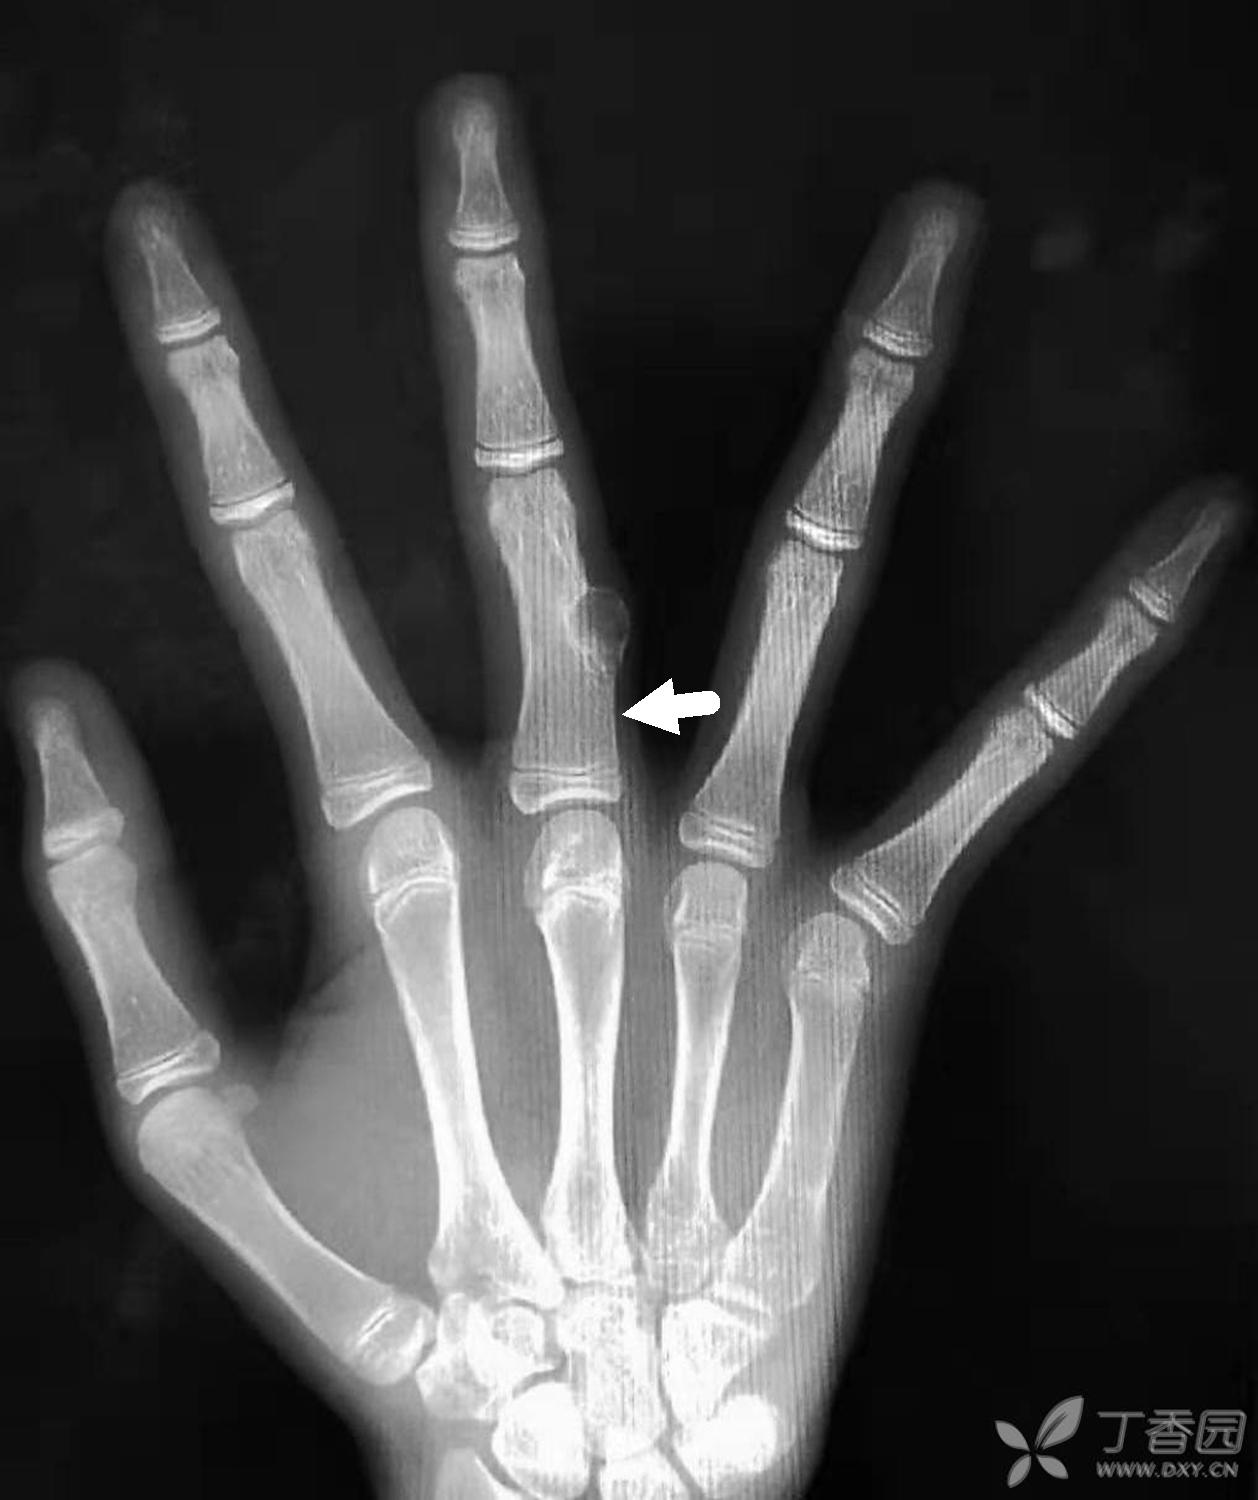

右手中指近节指骨中段尺侧骨皮质可见一膨胀性骨质破坏,病灶内

图片尺寸1258x1500